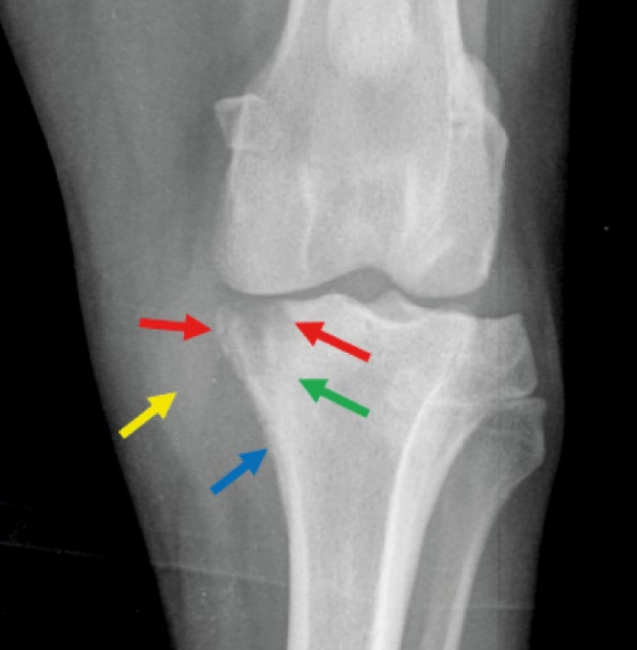

- ๊ด์ ์์ธก์์ ๋ผ์ ๋ณํ๊ฐ ๋ํ๋จ - subchondral bone & cortex์ lysis, new bone production

![]() | - ๋๋ ทํ๊ฒ ๋ํ๋๊ธฐ ์์ํ ๋ถ์. ํ๋ฆฟํ๊ฒ ํผ์ ธ ์๋ ๋ถ๋ถ. |

![]() | - density๋ ๋จ์ด์ ธ ์์ |